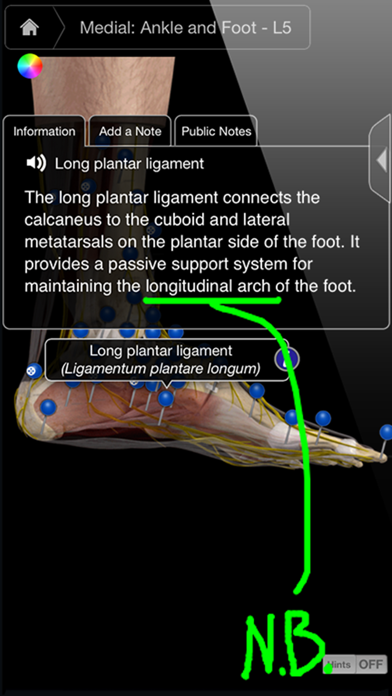

1. Ankle & Foot Pro III provides multiple cross sections (Sagittal, Coronal and Transverse) as well as the ability to cut away different layers revealing the muscles, blood vessels, nerves and connective tissue down to the skeleton.

2. • Multiple 3D cross sections (Sagittal, Coronal, and Transverse) and the ability to cut away different layers down to the bone.

3. • Double Tap to zoom: Zoom in to and identify any part of the ankle & foot by tapping on the screen.

6. This app’s primary use is as a learning tool and can also be used as a fast and innovative reference tool by utilizing the index function which allows the user to select any pin in the app -- and the app will automatically find and identify it.

7. • Each cross section shows muscle, nervous, vascular and skeletal systems with detailed information on each system - with the touch of a pin.